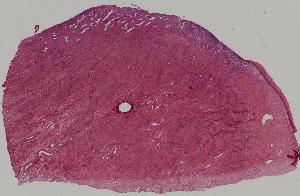

1.心肌褐色萎缩心肌肥大

2.肾曲管上皮混浊肿胀

3.肝细胞脂肪变性

4.脾包膜玻璃样变

5.血管壁纤维样坏死

6.肝细胞凝固性坏死

7.脑液化性坏死

10.肝淤血

11.淤血性肝纤维化

12.急性肺淤血

13.慢性肺淤血

14.混合血栓

15.机化血栓

16.肾贫血性梗死

17.肺出血性梗死

18.假膜性肠炎

19.蜂窝织性阑尾炎

20.肺脓肿

21.慢性扁桃体炎

22.慢性宫颈炎

第一页